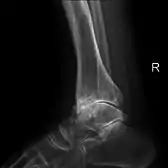

Diagnosis is made with reasonable certainty based on history and clinical examination.[41][42] X-rays may confirm the diagnosis. The typical changes seen on X-ray include: joint space narrowing, subchondral sclerosis (increased bone formation around the joint), subchondral cyst formation, and osteophytes.[43] Plain films may not correlate with the findings on physical examination or with the degree of pain.[44] Usually other imaging techniques are not necessary to clinically diagnose osteoarthritis.

Severe osteoarthritis and osteopenia of the carpal joint and 1st carpometacarpal joint.

Primary osteoarthritis of the left knee. Note the osteophytes, narrowing of the joint space (arrow), and increased subchondral bone density (arrow).